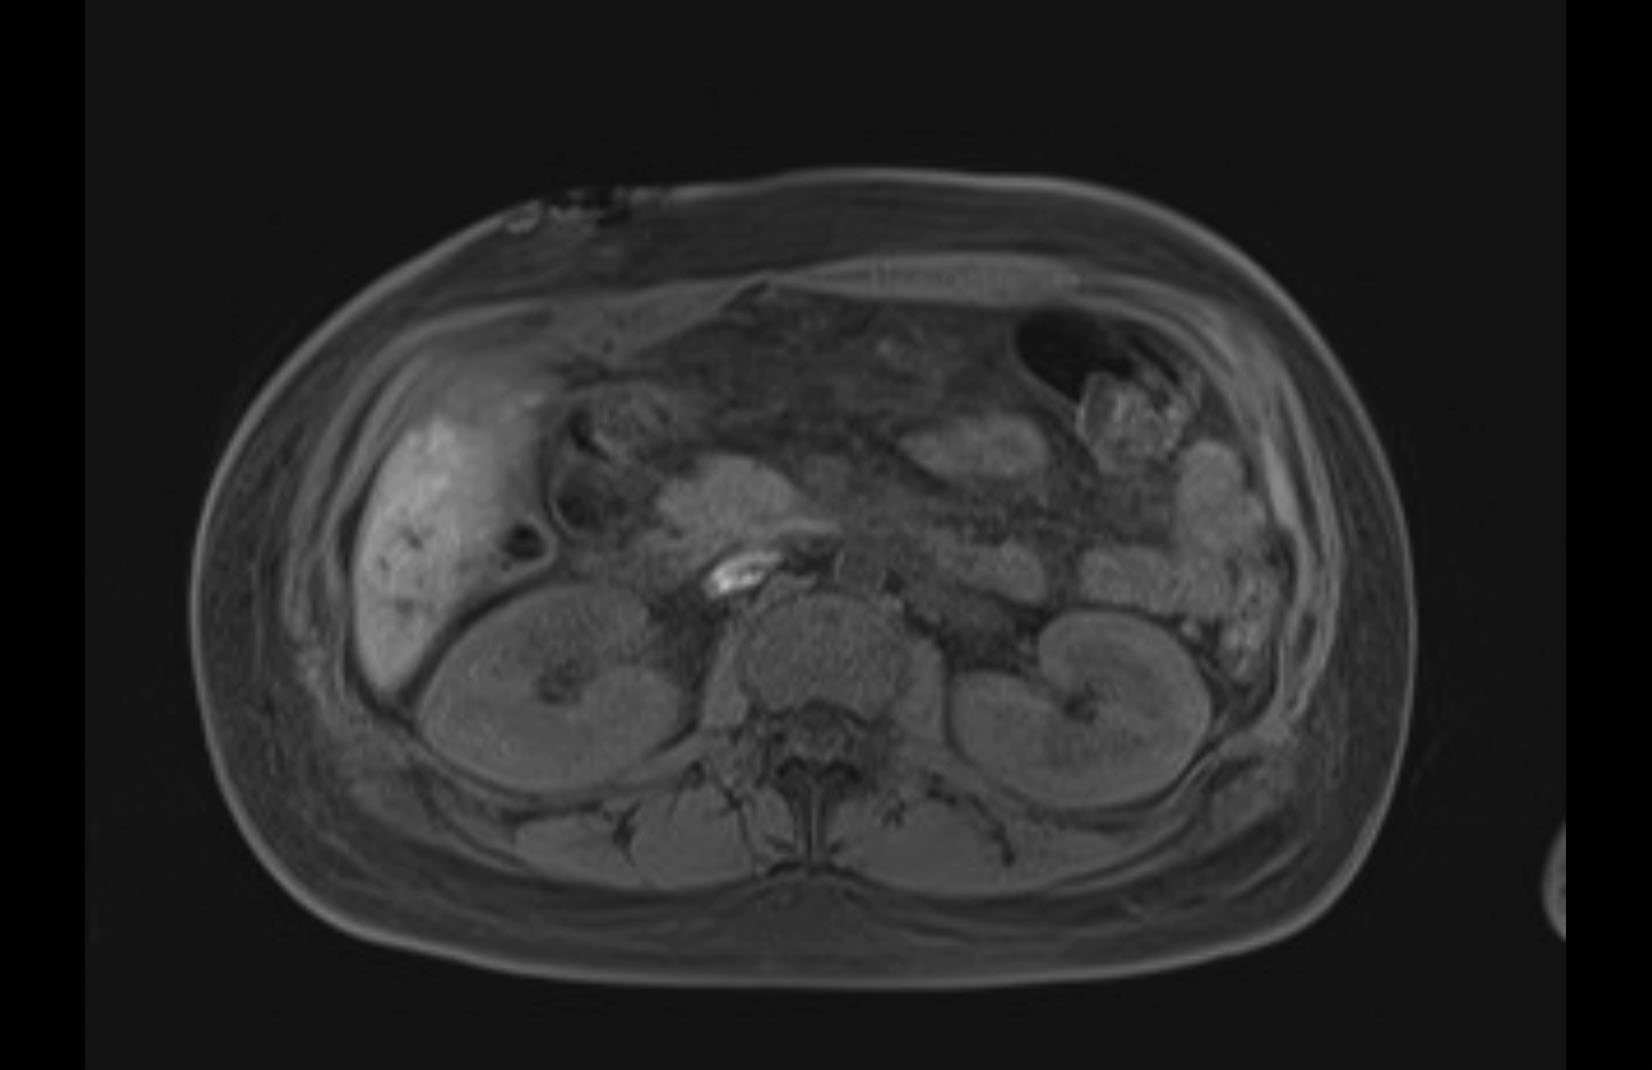

Imaging Analysis

Look through the patient's CT scan to identify any areas of concern for the necessary procedure.

MRI T2

Based on initial findings, which issue(s) would you be most concerned about?